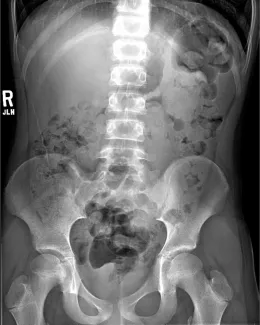

Abdominal Xrays are necessary to evaluate the effectiveness of the laxative or enema therapy and to identify the amount of stool in the colon. These will be done at each office visit.